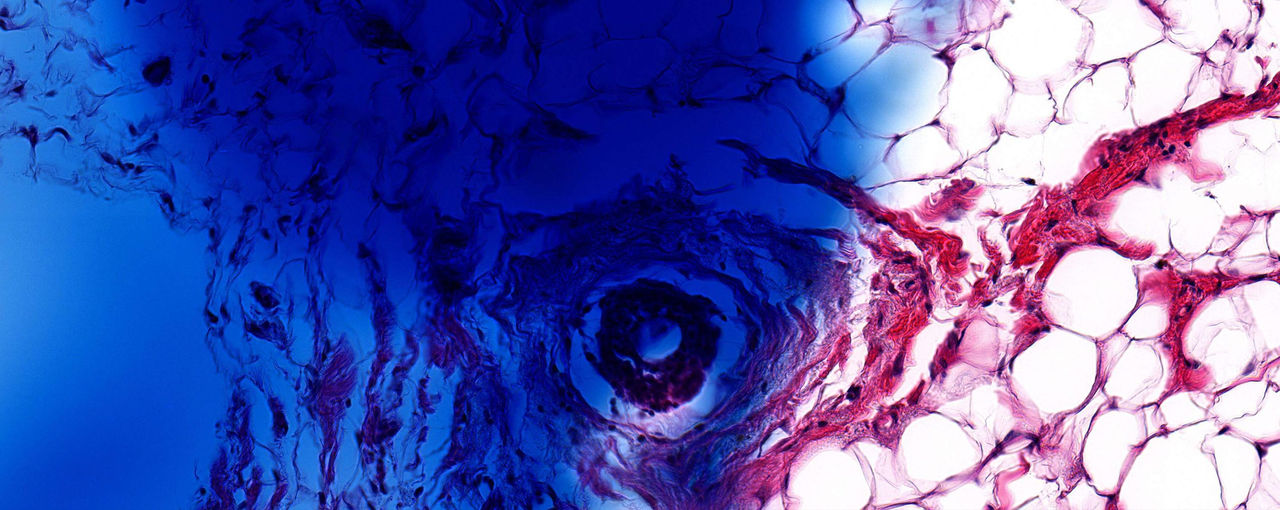

Every two years, ACS sent participants a follow-up questionnaire, and if someone reported that they had breast cancer, their hospital would send tumor samples to ACS. The samples were made by soaking the removed tumor in a solution that stops cellular activity, putting it in a block of wax, taking a very thin slice out of the block, staining the slice to show the different parts of the cells, and then putting the slice in a glass slide.

Since the study began, ACS has collected over 1,700 slides from women diagnosed with breast cancer. These slides can provide critical clues to help prevent and treat breast cancer—but identifying those clues was a challenge.

The next step was to scrub the tissue slides of any inconsistencies that could skew the analysis. A lot has changed since 1992 in terms of how pathologists treat the slides. In the 90s, pathologists mixed the tissue dye by hand, which means there’s been a lot of color variations in the slides over the years. “We had some slides that were a light pink and some that were a dark purple,” says Gaudet. Also, some pathologists would write directly on the slides with Sharpies, circling a tumor or making notes.

Once we flagged and filtered out any irrelevant markings or coloring, we were able to set up unsupervised machine learning. We told the machine to identify patterns in the tiles and create 10 clusters. Clustering is when the machine groups similar patterns, like your phone automatically searching through your photos and creating a photo album of your daughter.

The machine created some clusters that the team understood, like identifying the grade of cancer, which validated that the machines were on track. “But there are also new patterns that we’re not yet unable to understand why they were clustered, which was the goal,” says Gaudet. “For example, clusters two and three—well, to my eye they look exactly the same but that’s the whole premise of the project, for the machine to identify differences that the human eye can’t.”